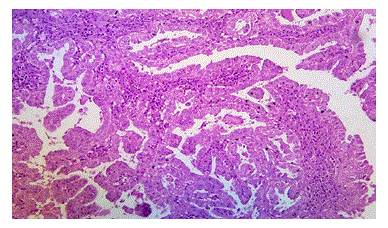

Illustrations

Figure 6: Photomicrograph Showing Papillary Thyroid Carcinoma, H&E, 100X (case no: 50)

Figure 7: Photomicrograph Showing Papillary Thyroid Carcinoma with Moderate and Diffuse Cytoplasm Positivity for BRAF V600E